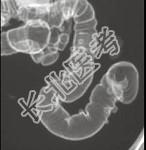

- 单项选择题男,52岁, 习惯性便秘2年余,结合图像, 应诊断为 ( )

A、溃疡性结肠炎

B、结肠憩室病

C、假膜性结肠炎

D、结肠息肉病

E、结肠转移瘤